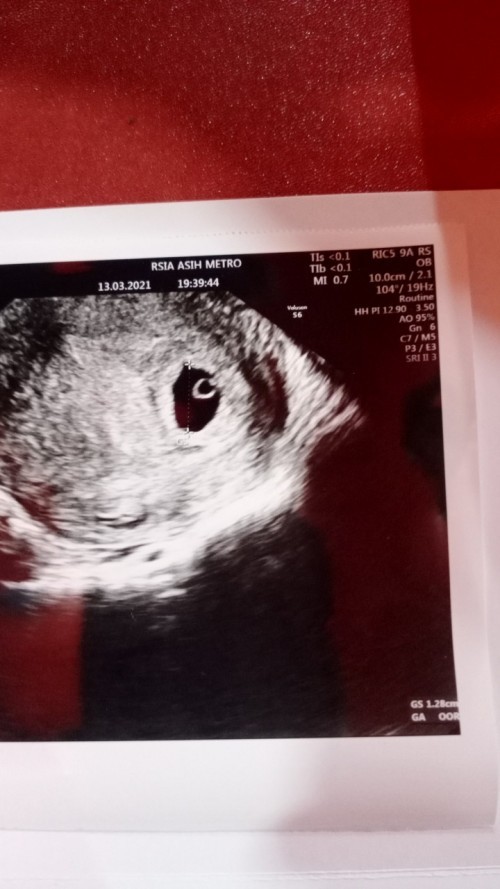

ini aku 8week bund, detaknya juga sudah ada.. tp kembali lagi, setiap kehamilan beda2 bund. tetep semangat dan selalu afirmasi positif ke diri sendiri dan ke janin🤗

pas kemarin awl itu aq usg 7 W udh kelihatan janin n detak jantung si bun. coba usg tranv bun. tetap optimis n positifthinking yaa bun 😊😊😊

itu kayak udh ada deh bun tapi kecil, kalo ga ada flek atau pendarahan gpp tunggu 2 minggu usg lagi aja kalo blm keliatan minta usg trans v